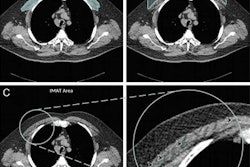

- Abnormal chest CT showing emphysema, gas trapping, and/or airway wall thickening